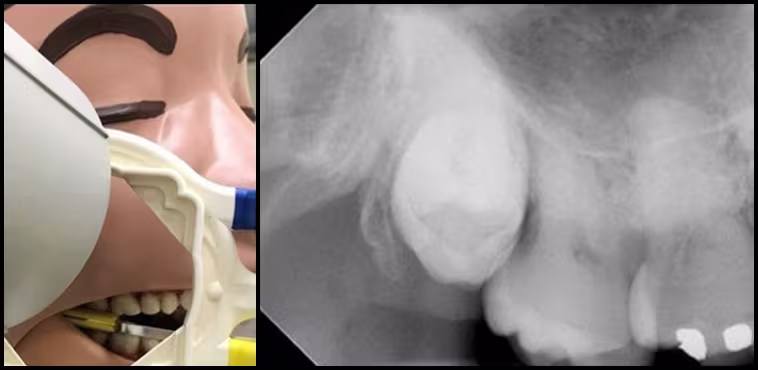

Solution: The sensor does not have to be placed so far posterior that the patient is uncomfortable. Remember the path of radiation statement one more time: The path of radiation must include the area of interest (teeth and surrounding bone) and active sensor. Change the path to cross the area from behind. Position the tubehead towards the ear and set the horizontal angulation of the radiation path forward across the most distal molar. The sensor can be placed as far posterior in the mouth as is comfortable. The interproximal contacts will be overlapped, but the root apices of the molars will be visible (Figure 35).

Figure 35 - Distal Molar Periapical.

Redirecting the PID posterior to the aiming ring to ensure coverage of radiation over the Maxillary third molar and distal tuberosity.